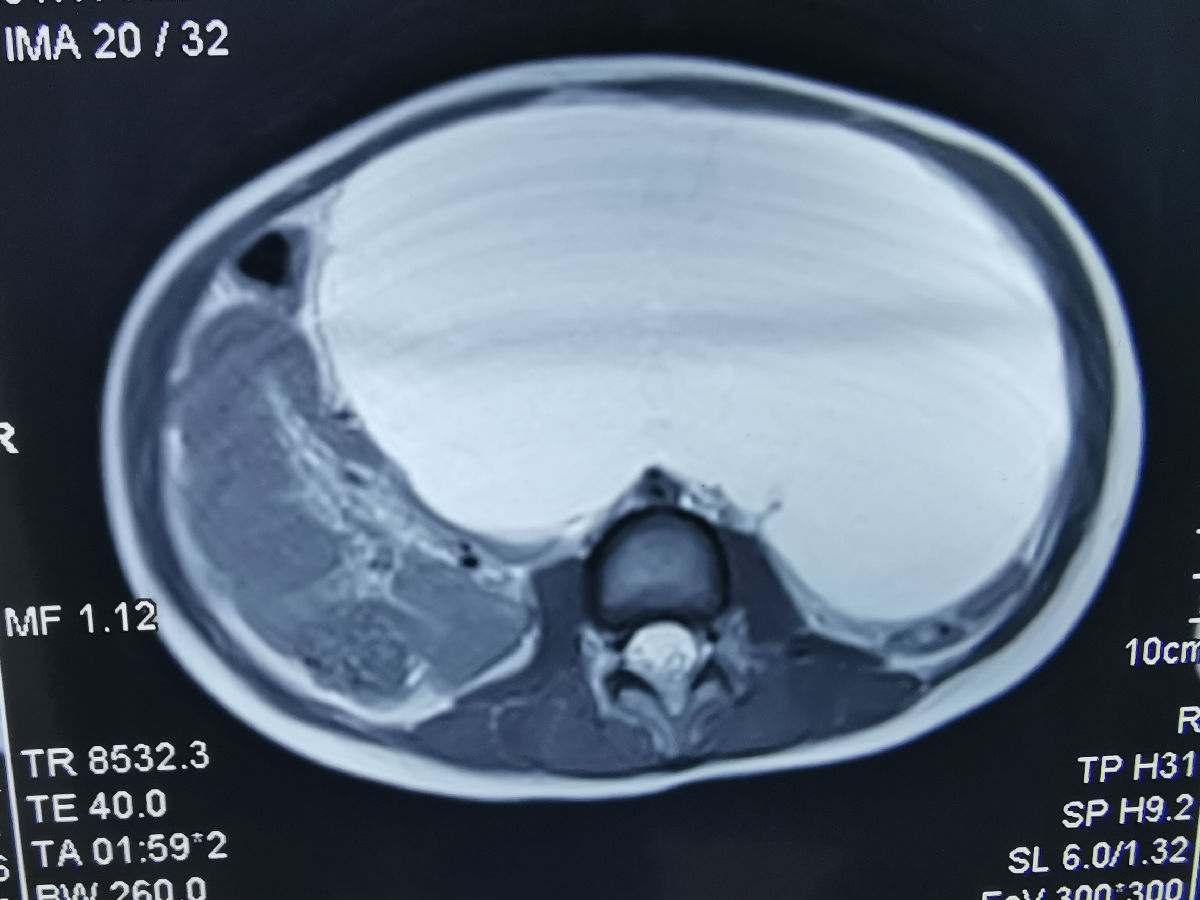

12月26日,儿童心血管科通过多学科协作完成了一例腹腔巨大淋巴管畸形的微创治疗。该5岁患儿腹腔包块巨大,压迫腹腔及腹膜后器官,之前辗转两家医院均未得到治疗。考虑到患儿年龄小,开腹治疗创伤大,经儿童心血管科与小儿外科、超声科讨论后,决定联合进行腹腔置管引流及介入硬化术。术中患儿在超声引导下顺利完成腹腔穿刺置管,引流出1000ml囊液,并在DSA引导下进行了硬化剂注射治疗。